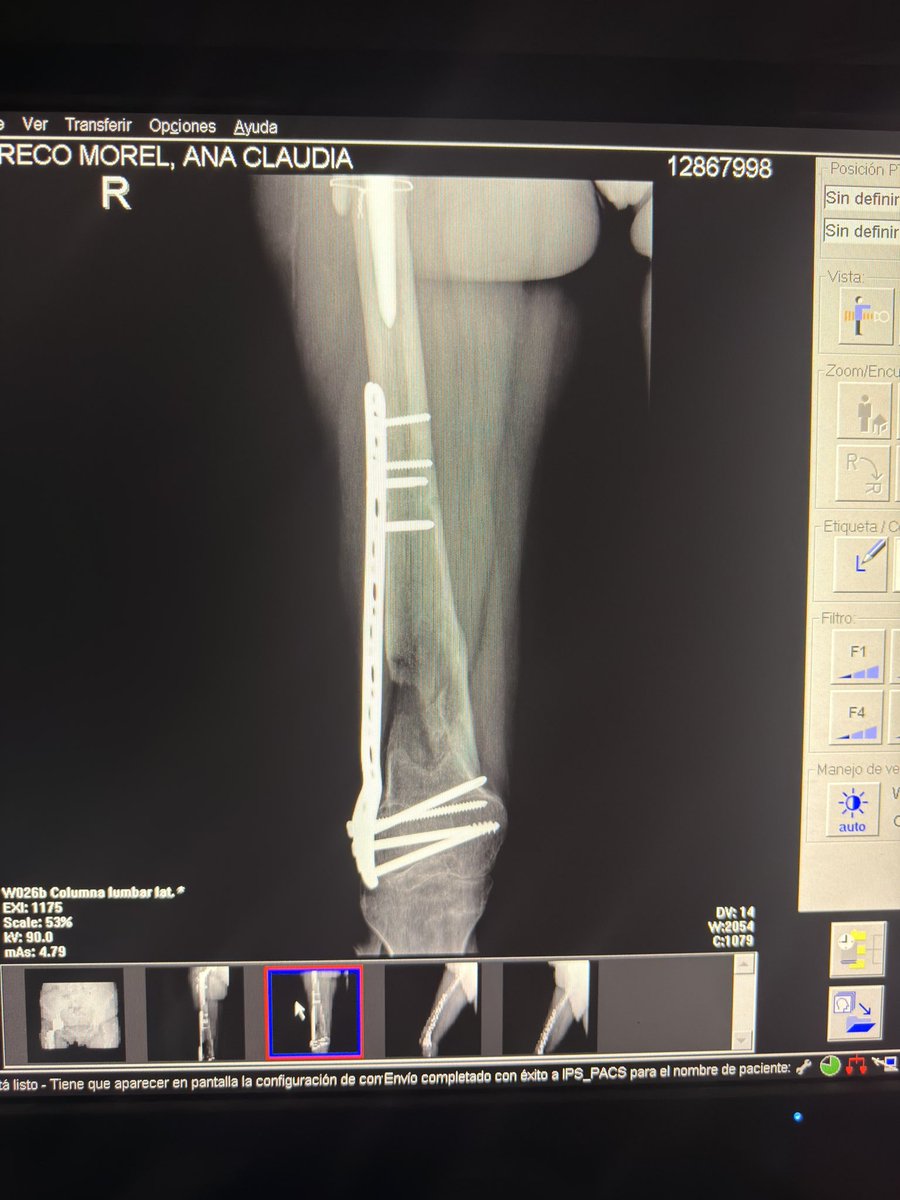

Essas sao as minhas radiografias, da pra ver o meu nome. Como o joelho nao esta dobrando (ja foram 5 cirurgias) eu nao consigo dirigir e ir com frequência nos correios e por isso uma menina se dispôs a fazer uma CEG de todas as minhas coisas ✨🩵 Estarei passando o contato dela.